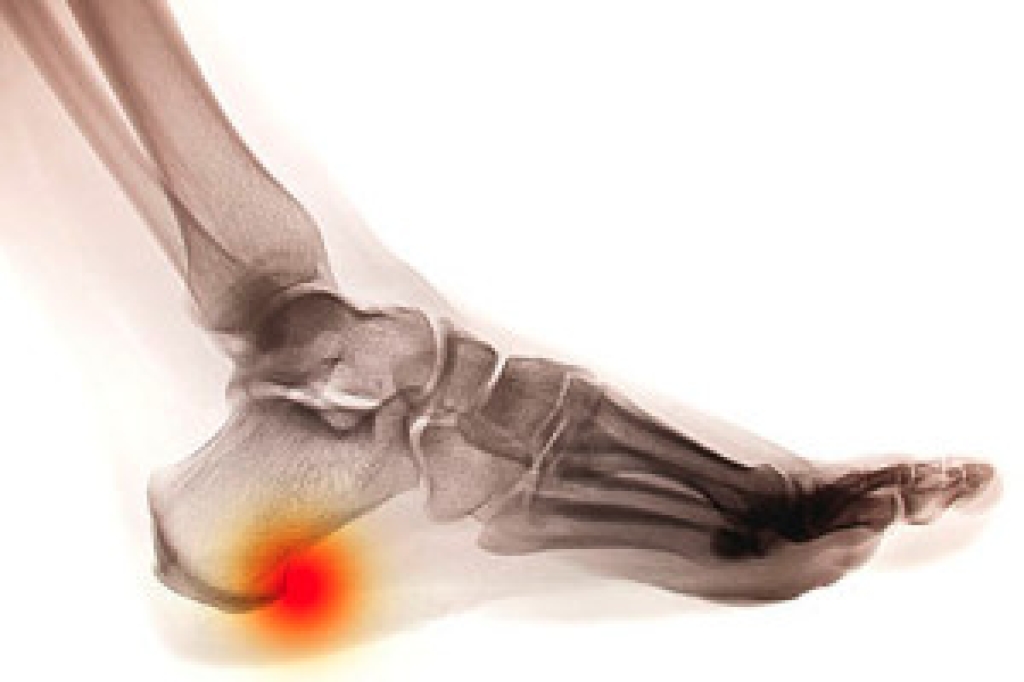

Those who enjoy hiking as a regular activity should be sure to employ foot care while on the trail to avoid potential pain and injury. The first step to maintaining proper foot care while hiking is to be aware of one’s surroundings. Many hiking-related foot injuries and conditions often occur as a result of not being aware while on the trail: rolled ankles, broken toes, and blisters. When hiking, be sure to wear shoes that are breathable and that either dry quickly or are waterproof. When trying on hiking boots or shoes, finding a great fit is important. With modern innovations in footwear, hiking boots are becoming lighter and more comfortable.

It is best to check your feet regularly to make sure there are no new bruises or cuts that you may not have noticed before. For dry feet, moisturizer can easily be a remedy and can be applied as often as necessary to the affected areas. Wearing shoes that fit well can also help you maintain good foot health, as well as making it easier to walk and do daily activities without the stress or pain of ill-fitting shoes, high heels, or even flip flops. Wearing clean socks with closed shoes is important to ensure that sweat and bacteria do not accumulate within the shoe. Clean socks help to prevent Athlete’s foot, fungi problems, bad odors, and can absorb sweat.